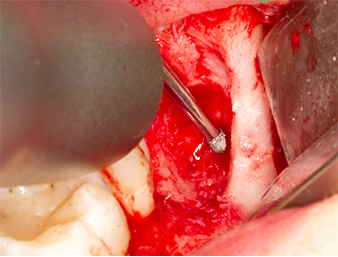

Um autogenes Material für die spätere Wundversorgung zu gewinnen, wurden mit einem piezochirugischen Instrument (Piezomed B5) gesunde Knochenspäne aus der Umgebung des Wurzelrests gewonnen (Abb. 5).

Das autogene Gewebe wurde mit dem schaufelförmigen Arbeitsteil des Instruments entnommen und bis zur weiteren Verwendung in physiologischer Kochsalzlösung aufbewahrt (vgl. Abb. 13).